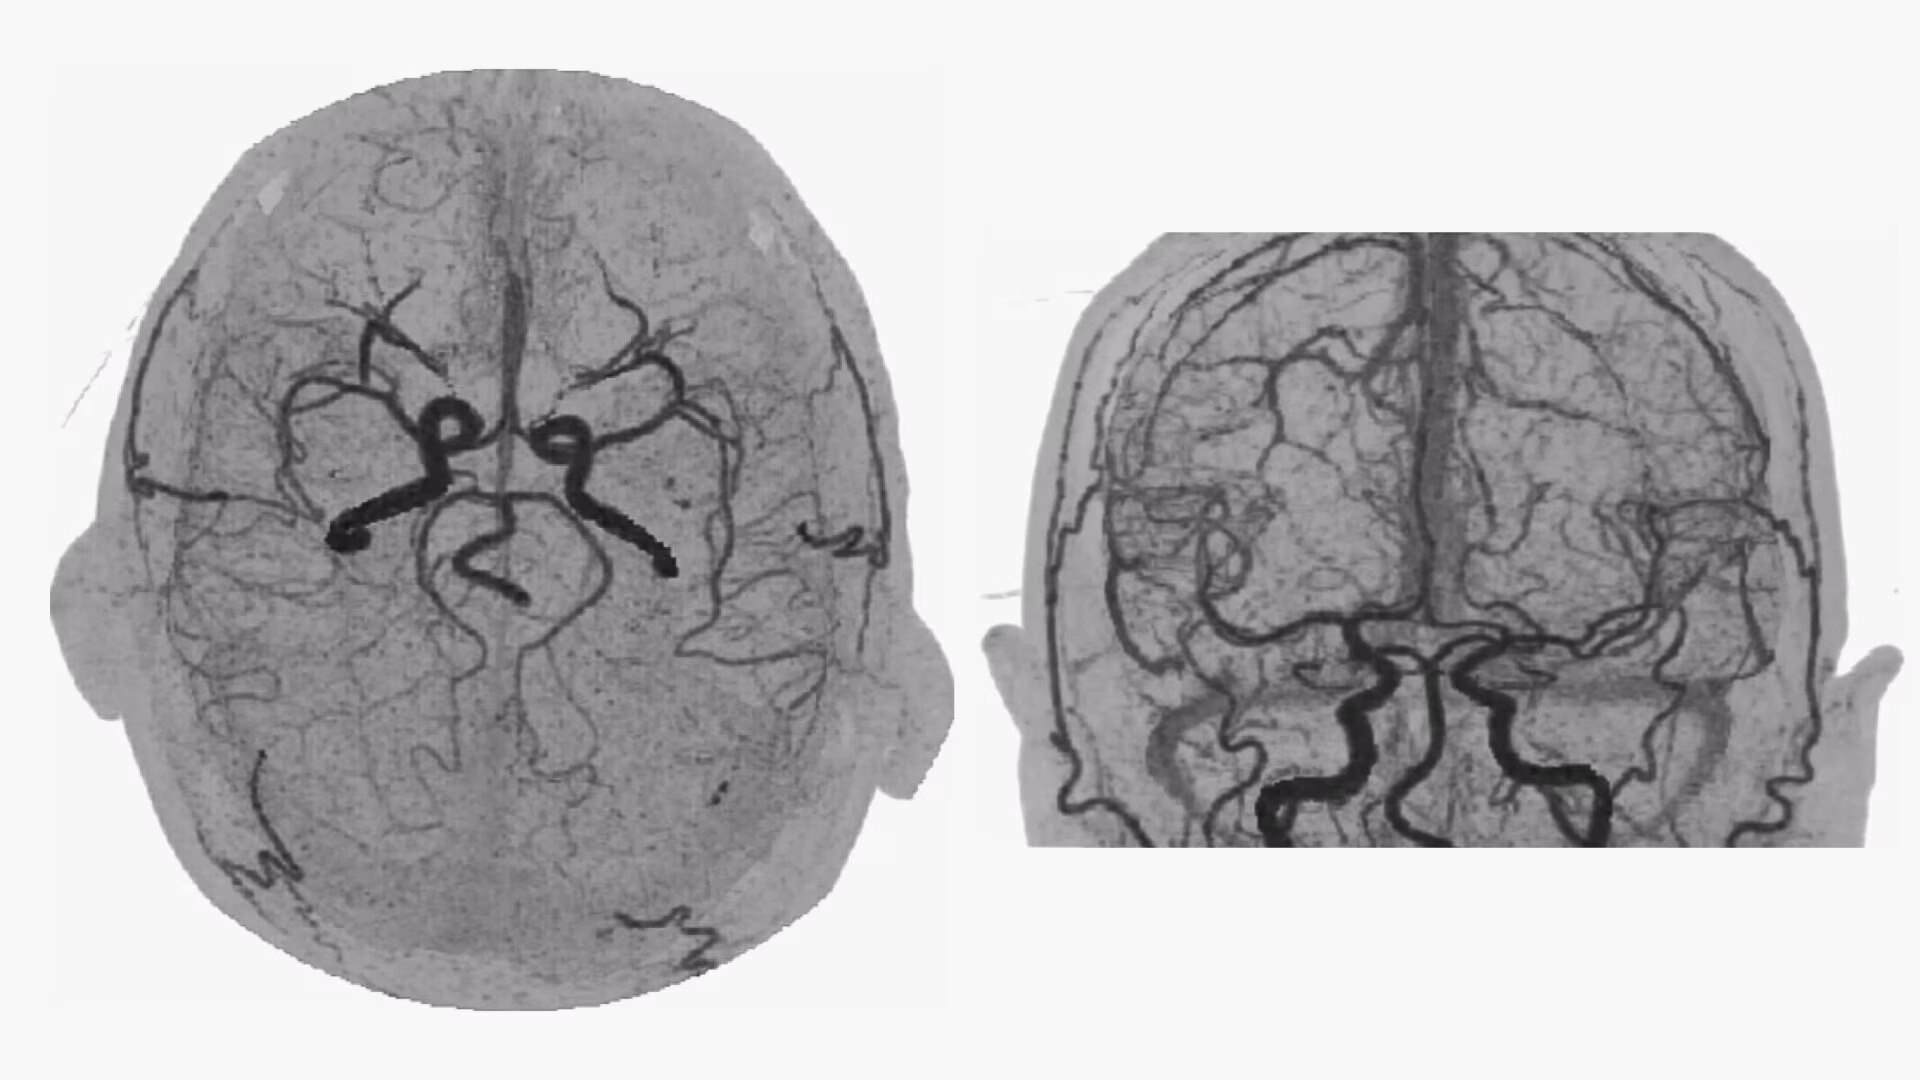

Bone-free dynamic visualization of vascular anatomy.

• 4D Neuro Digital Subtraction angiography (DSA) automatically performs image registration, then removes bone.